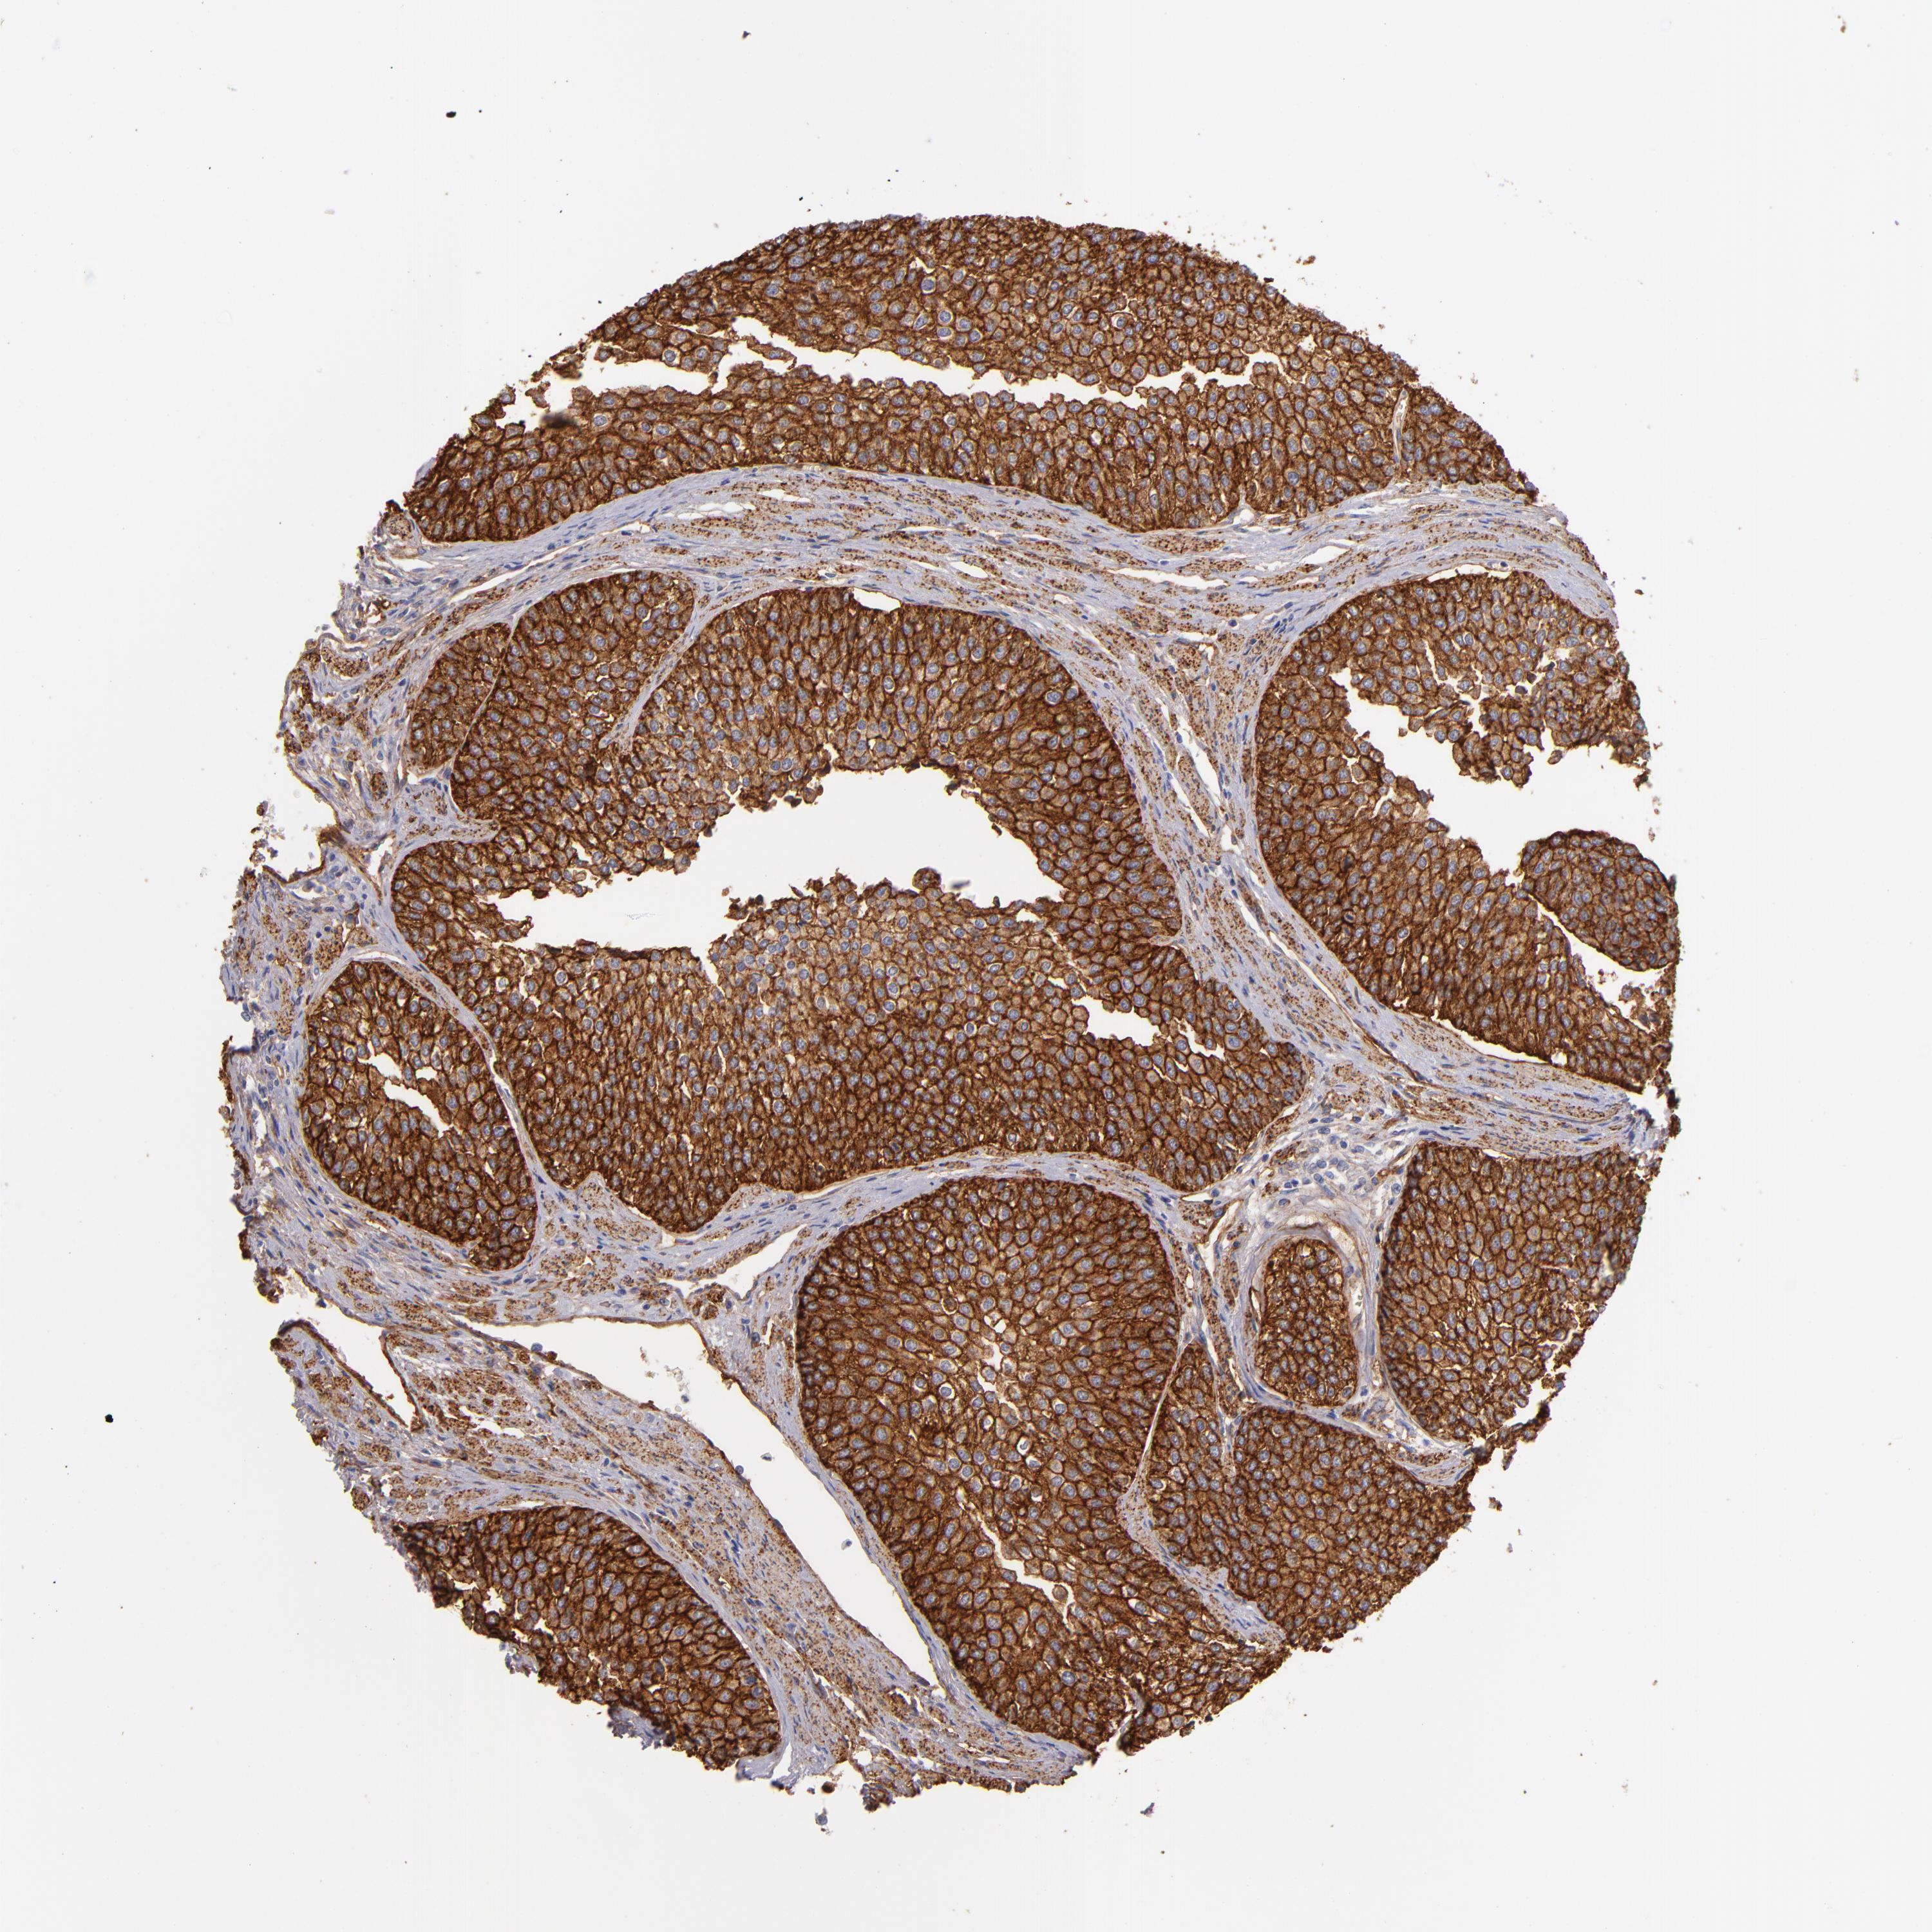

UROTHELIAL CANCER - Protein expressioni

A mouse-over function shows sample information and annotation data. Click on an image to view it in a full screen mode. Samples can be filtered based on level of antibody staining by selecting one or several of the following categories: high, medium, low and not detected. The assay and annotation is described here.

Note that samples used for immunohistochemistry by the Human Protein Atlas do not correspond to samples in the TCGA dataset.

Antibody stainingi

Antibody staining in the annotated cell types in the current human tissue is reported as not detected, low, medium, or high, based on conventional immunohistochemistry profiling in selected tissues. This score is based on the combination of the staining intensity and fraction of stained cells.

Each image is clickable and will lead to virtual microscopy that enables deeper exploration of all samples and also displays staining intensity scores, fraction scores and subcellular localization as well as patient and tissue information for each sample.

Antibody HPA011906

Antibody CAB002428

Urothelial carcinoma, Low grade

Urothelial carcinoma, High grade

Adenocarcinoma, NOS